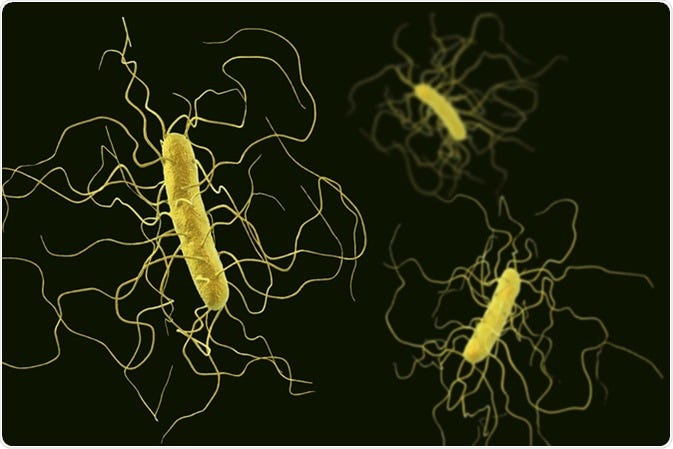

Clostridium difficile

Clostridium difficile

And talking about faecal transplantation, there are at least 15 stool banks in the world right now, with the Openbiome in U.S.A. being the biggest. The stools can be used in treating Clostridium difficile, assisting in research for IBS and some other diseases. Only 2.5% of the potential donors are suitable after they are tested. In Netherlands for example, the stool bank has only 8 active donors and they treated 70–80 patients until now.